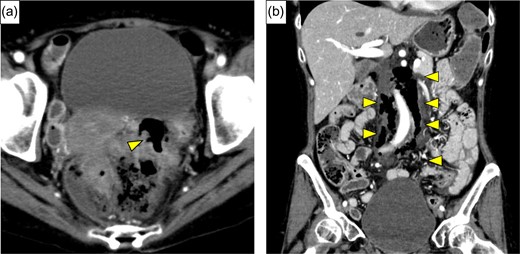

A 54-year-old woman was referred to our hospital because of abdominal pain. She had a history of adult Still’s disease at age 49 and underwent treatment with oral prednisolone, 90 mg/day and cyclosporine, 175 mg/day. A physical examination revealed deep tenderness in the abdomen. Laboratory data showed slight leukocytosis (white blood cell count 9100/μL) with a moderately elevated C-reactive protein level (9.3 mg/dL), while other data, including blood coagulation factor, were within normal ranges. Computed tomography (CT) revealed a small amount of extra-intestinal free air around the rectum and massive retroperitoneal emphysema between the rectum and the left kidney (Fig. 1a and b). Arterial aneurysm was not confirmed. Based on a preoperative diagnosis of rectal perforation, emergency laparotomy was performed, which confirmed peritoneal fluid collection (Fig. 2) and rectum perforation on the retroperitoneal side. After aspiration of the pus and irrigation of the area with saline, Hartmann’s operation was performed (Fig. 3a). Although she was undergoing immunosuppressive treatment, pathological study disclosed no association between diverticulum perforation and cytomegalovirus enteritis (Fig. 3b). On postoperative Day 4, she suffered a sudden intolerable left flank pain; her hemoglobin level was 7.5 g/dL, and slight prolongation of prothrombin time was recognized. CT revealed a left retroperitoneal hematoma and extravasation from the left first lumbar arteries (Fig. 4a). Emergency transarterial angiography and lumbar artery embolization was performed (Fig. 4b). On Day 20 after the first operation the patient felt a sudden right flank pain, and CT confirmed intra-abdominal free air (Fig. 5a). A second emergency laparotomy was performed, which revealed cecal perforation with no obvious masses (Fig. 5b). Perforation resulting from diverticulum was suspected, and an ileostomy without intraperitoneal anastomosis was performed because of concern about anastomotic leakage. Postoperatively the patient developed an intra-abdominal abscess, surgical site infection (Clavien-Dindo IIIa) and pneumonia (Clavien-Dindo II), which were treated conservatively. Although it took time to rehabilitate the patient and control the adult Still’s disease, she was discharged on Day 212 after the first operation. The patient is now doing well with comfortable activity of daily life.

(a) The resected specimen showed perforation at the rectum (red arrow), and diverticulitis was apparent (yellow arrows). (b) A photomicrograph showed diverticulum perforation over the posterior wall of the rectum (red arrow).